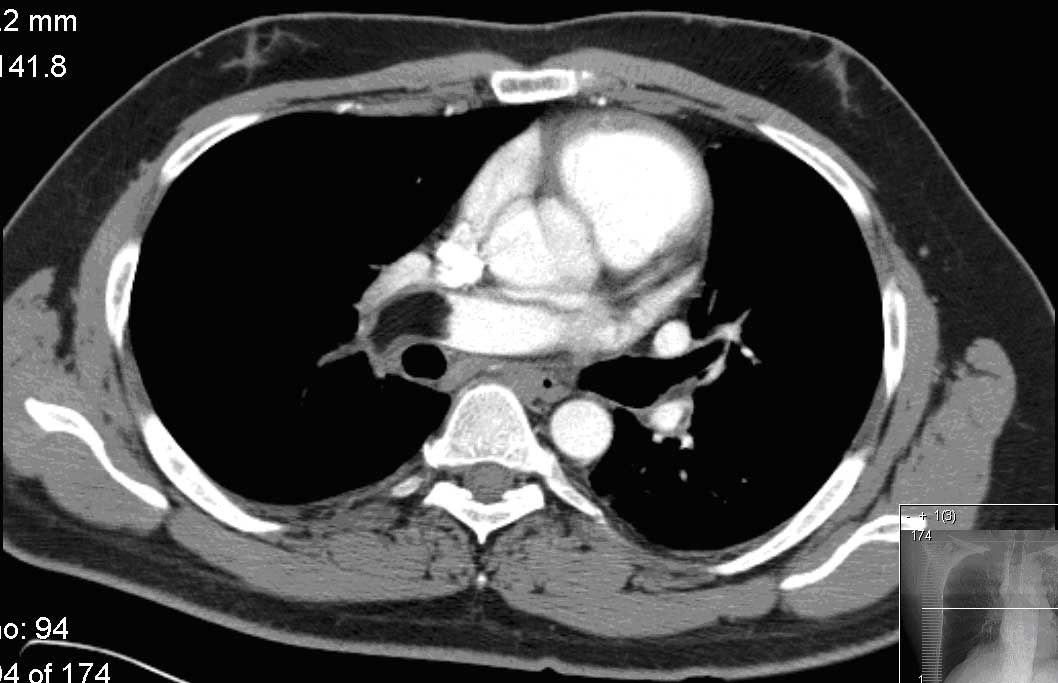

Computed tomography angiogram of the chest with intravenous iodinated contrast

D. The patient presented with acute dyspnea, mild hypoxemia, and constitutional symptoms. His D-dimer was negative but the computed tomography (CT) angiogram of his chest revealed an acute filling defect in the right pulmonary artery with the density of fat. The history and the density of filling defect argue strongly against an air embolism. The density of the acute filling defect is not consistent with a thrombus.

The fat density acute filling defect seen in the pulmonary artery is most consistent with an acute tumor embolism from a primary tumor with a high proportion of fat (2, 3).